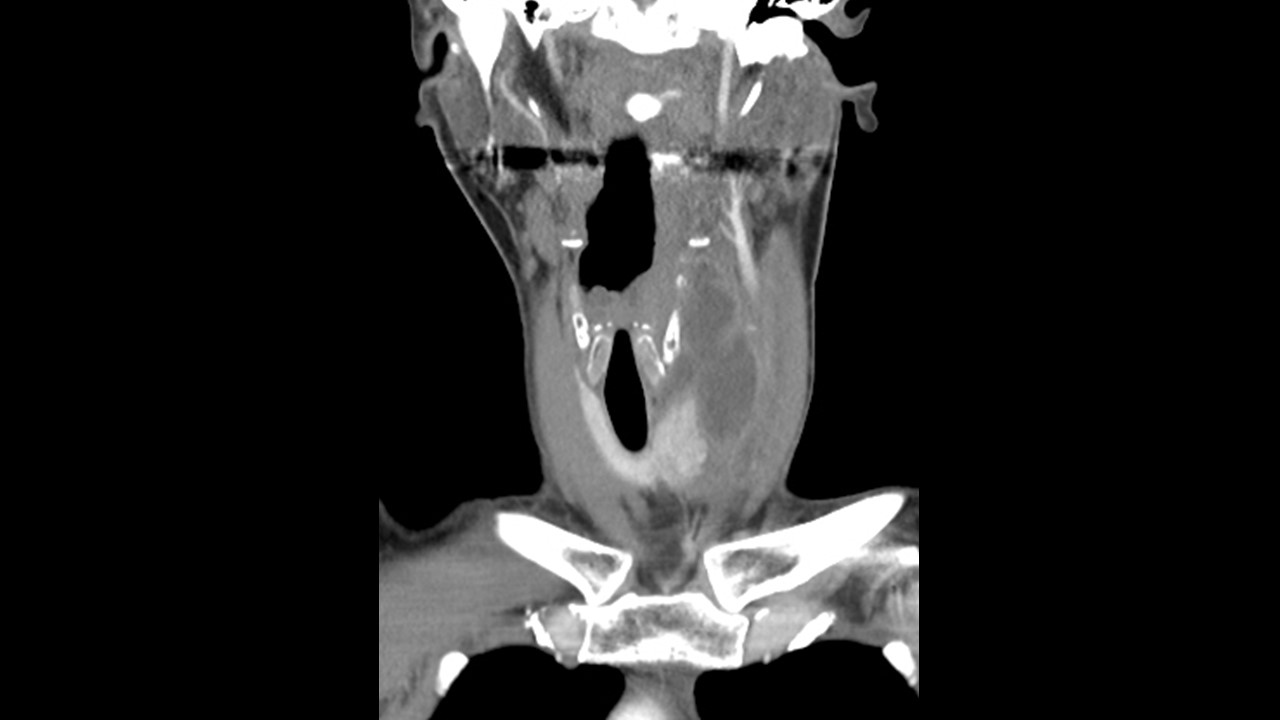

[369,] 48/F,Sore throat, neck pain

Modality

US,CT,

What is the most likely diagnosis?

[Diagnosis]

1.

Hypopharynx cancer with thyroid invasion

2.

Infected 4th branchial cleft anomaly

3.

Infected thyroglossal duct cyst

4.

Anaplastic thyroid cancer

5.

Infected 3rd branchial cleft anomaly